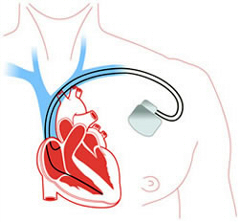

Der ICD (implantierbarer Cardioverter Defibrillator) ist ein Gerät, das Patienten mit hohem Risiko für lebensbedrohliche Herzrhythmusstörungen implantiert wird.

Er ist Schrittmacher und Defibrillator in einem. Schlägt das Herz zu langsam, gibt das Gerät leichte Impulse ab, um die Pumpleistung konstant zu halten.